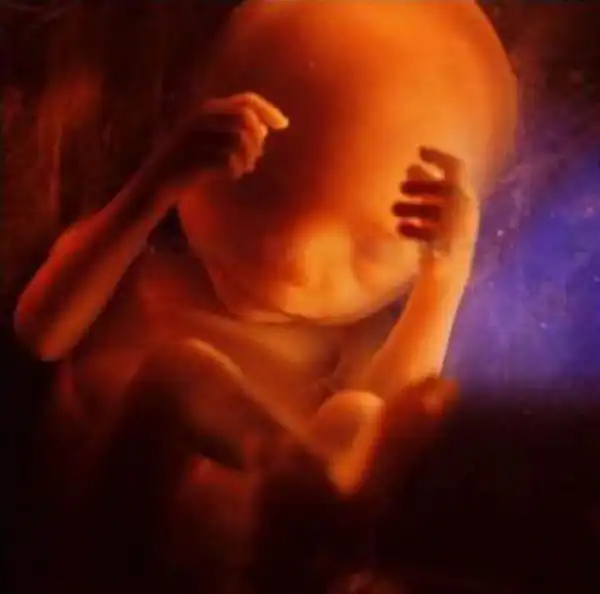

18 недель. Около 14 см. Зародыш теперь может воспринимать звуки из внешнего мира.

19 недель..

20 недель. Около 20 см. На голове уже начинают появляться волосы.

24 недели..

26 недель...

6 месяцев. Впереди еще восемь-десять беззаботных недель, но человечку уже тесно в матке, и он готовится покинуть ее. Поворачивается вниз головой - так удобнее выбраться..

36 недель. Через 4 недели ребенок увидит белый свет